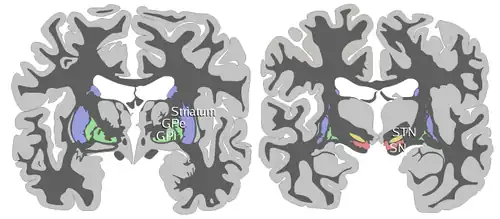

The substantia nigra (SN) is a basal ganglia structure located in the midbrain that plays an important role in reward and movement. Substantia nigra is Latin for "black substance", reflecting the fact that parts of the substantia nigra appear darker than neighboring areas due to high levels of neuromelanin in dopaminergic neurons.[1] Parkinson's disease is characterized by the loss of dopaminergic neurons in the substantia nigra pars compacta.[2]

Although the substantia nigra appears as a continuous band in brain sections, anatomical studies have found that it actually consists of two parts with very different connections and functions: the pars compacta (SNpc) and the pars reticulata (SNpr). The pars compacta serves mainly as a projection to the basal ganglia circuit, supplying the striatum with dopamine. The pars reticulata conveys signals from the basal ganglia to numerous other brain structures.[3]

The substantia nigra, along with four other nuclei, is part of the basal ganglia. It is the largest nucleus in the midbrain, lying dorsal to the cerebral peduncles. Humans have two substantiae nigrae, one on each side of the midline.

The SN is divided into two parts: the pars reticulata (SNpr) and the pars compacta (SNpc), which lies medial to the pars reticulata. Sometimes, a third region, the pars lateralis, is mentioned, though it is usually classified as part of the pars reticulata. The (SNpr) and the internal globus pallidus (GPi) are separated by the internal capsule.[4]

The pars reticulata bears a strong structural and functional resemblance to the internal part of the globus pallidus. The two are sometimes considered parts of the same structure, separated by the white matter of the internal capsule. Like those of the globus pallidus, the neurons in pars reticulata are mainly GABAergic.[5][6]

Afferent connections

The main input to the SNpr derives from the striatum. It comes by two routes, known as the direct and indirect pathways. The direct pathway consists of axons from medium spiny cells in the striatum that project directly to pars reticulata. The indirect pathway consists of three links: a projection from striatal medium spiny cells to the external part of the globus pallidus; a GABAergic projection from the globus pallidus to the subthalamic nucleus, and a glutamatergic projection from the subthalamic nucleus to the pars reticulata.[6][7] Thus, striatal activity via the direct pathway exerts an inhibitory effect on neurons in the (SNpr) but an excitatory effect via the indirect pathway. The direct and indirect pathways originate from different subsets of striatal medium spiny cells: They are tightly intermingled, but express different types of dopamine receptors, as well as showing other neurochemical differences.

Significant projections occur to the thalamus (ventral lateral and ventral anterior nuclei), superior colliculus, and other caudal nuclei from the pars reticulata (the nigrothalamic pathway),[8] which use GABA as their neurotransmitter. In addition, these neurons form up to five collaterals that branch within both the pars compacta and pars reticulata, likely modulating dopaminergic activity in the pars compacta.[9]